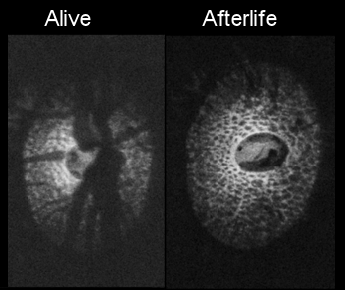

• Seeing the hidden lamina; Effects of exsanguination on the optic nerve head

• H Tran, J Wallace, Z Zhu, KA Lucy, AP Voorhees, SE Schmitt, RA Bilonick, JS Schuman, MA Smith, G Wollstein, and IA Sigal

• Investigative Ophthalmology and Visual Science, 59, 2564-2575, May 2018.

image